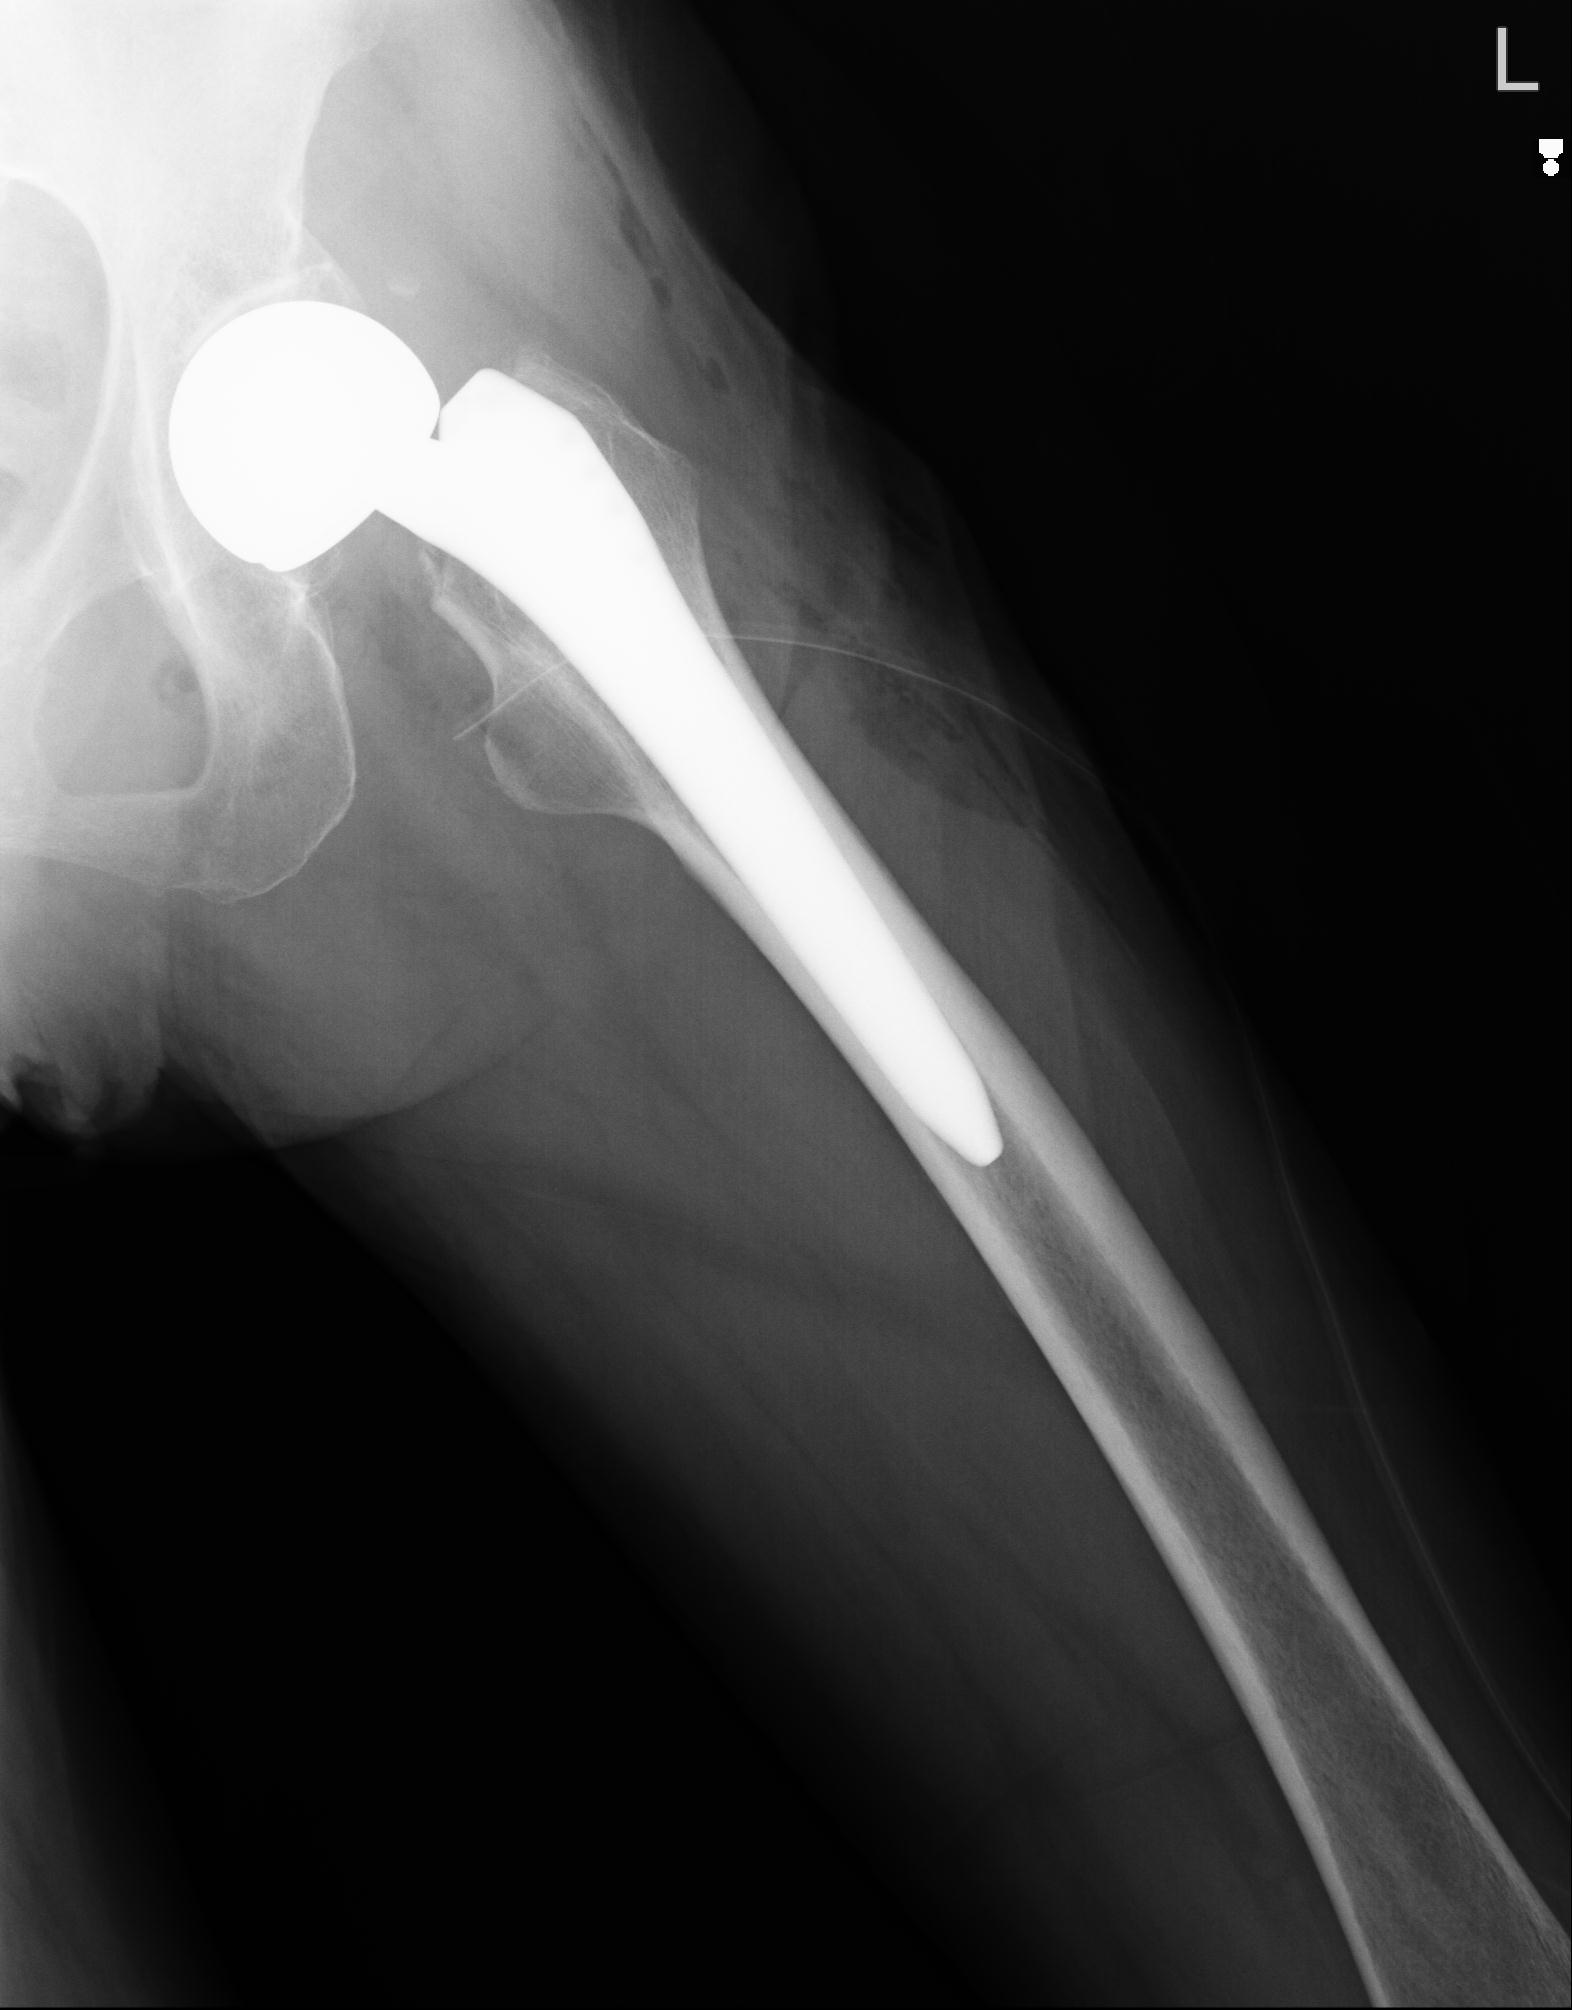

110286 2/17 股関節 2R 74歳女性 右人工骨頭

82084 1/14 1/20 股関節 2R 78歳男性 右人工骨頭

102811 1/13 股関節 2R 1/19 2R 80歳女性 右DHS

91569 3/25 両股正面とラウエン 70歳女性 人工骨頭+バンクーバー